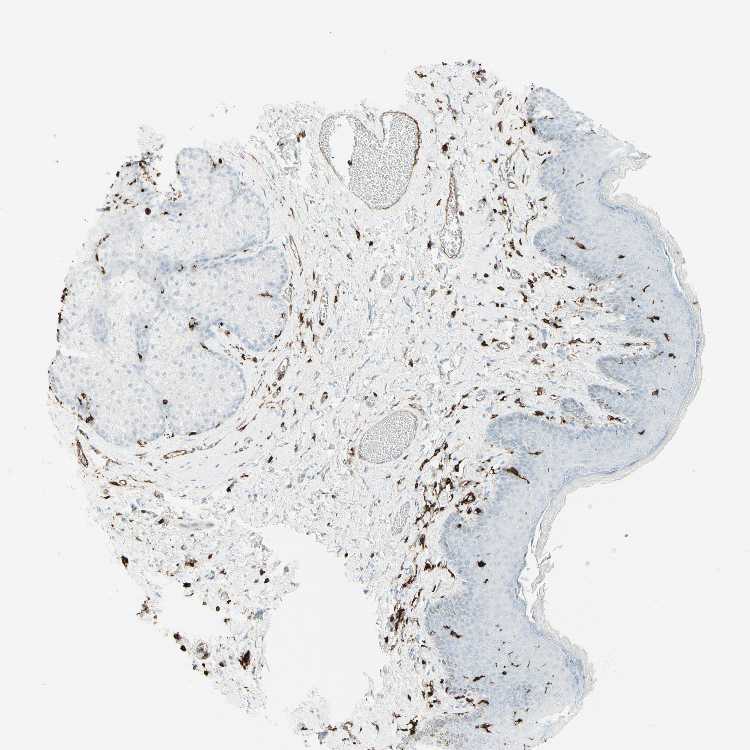

SKIN 1 - Antibody stainingi

Antibody staining in the annotated cell types in the current human tissue is reported as not detected, low, medium, or high, based on conventional immunohistochemistry profiling in selected tissues. This score is based on the combination of the staining intensity and fraction of stained cells.

Each image is clickable and will lead to virtual microscopy that enables deeper exploration of all samples and also displays staining intensity scores, fraction scores and subcellular localization as well as patient and tissue information for each sample.

Antibody HPA011078

Langerhans Medium

Fibroblasts Low

Keratinocytes Medium

Melanocytes Medium